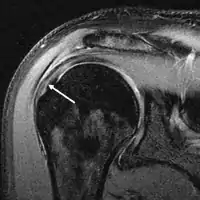

MRI

Magnetic resonance imaging (MRI) and ultrasound[41] are comparable in efficacy and helpful in diagnosis although both have a false positive rate of 15–20%.[42] MRI can reliably detect most full-thickness tears although very small pinpoint tears may be missed. In such situations, an MRI combined with an injection of contrast material, an MR-arthrogram, may help to confirm the diagnosis. It should be realized that a normal MRI cannot fully rule out a small tear (a false negative) while partial-thickness tears are not as reliably detected.[43] While MRI is sensitive in identifying tendon degeneration (tendinopathy), it may not reliably distinguish between a degenerative tendon and a partially torn tendon. Again, magnetic resonance arthrography can improve the differentiation.[43] An overall sensitivity of 91% (9% false negative rate) has been reported indicating that magnetic resonance arthrography is reliable in the detection of partial-thickness rotator cuff tears.[43] However, its routine use is not advised, since it involves entering the joint with a needle with potential risk of infection. Consequently, the test is reserved for cases in which the diagnosis remains unclear.